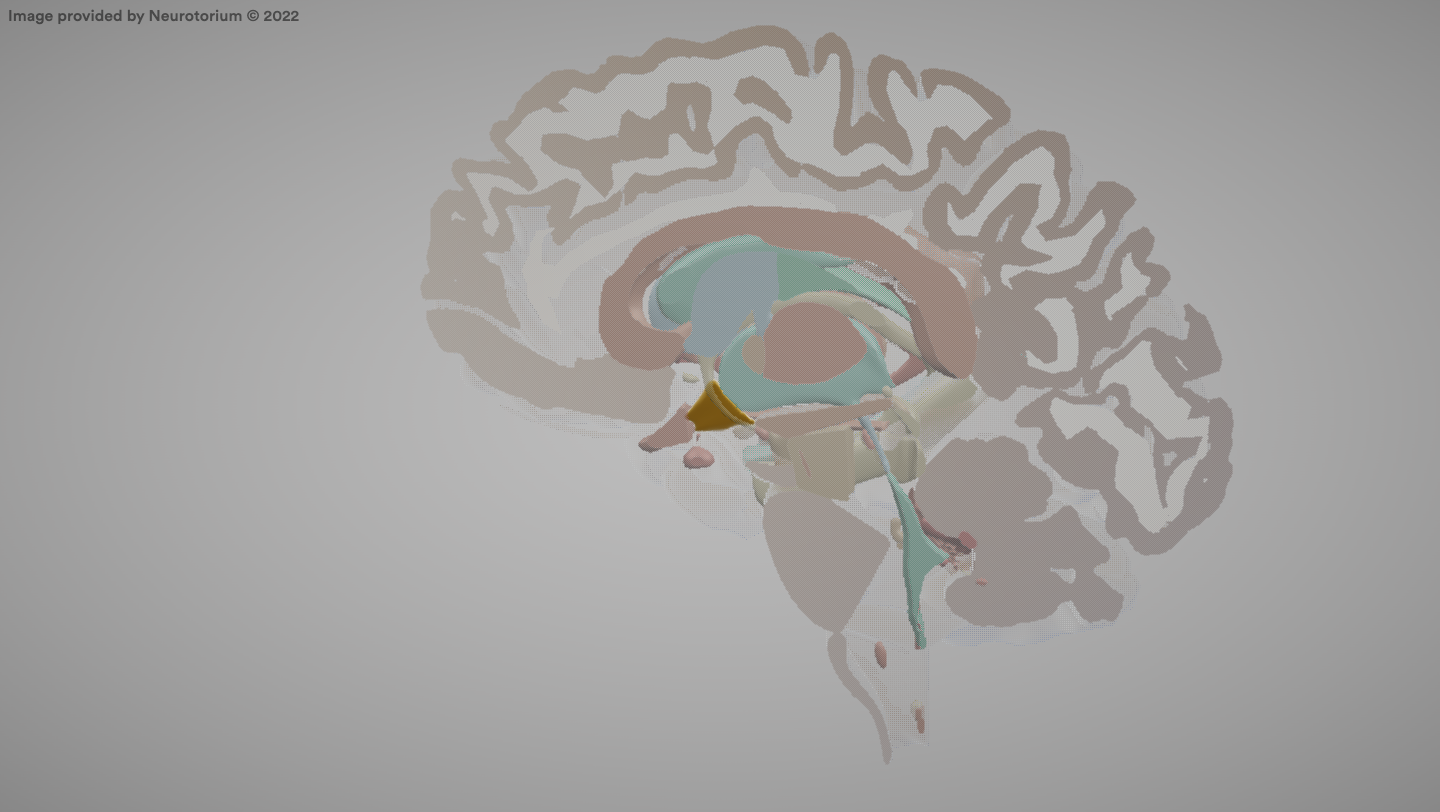

Hypofysen

The pituitary gland.

Hypothalamus

Brain region that regulates body temperature, hunger, thirst, and hormonal balance.

Thalamus

A brain structure that relays sensory and motor information to the cerebral cortex.

Corpus Callosum

A large bundle of nerve fibers connecting the two cerebral hemispheres.

Hippocampus

A brain structure involved in the formation of new memories.